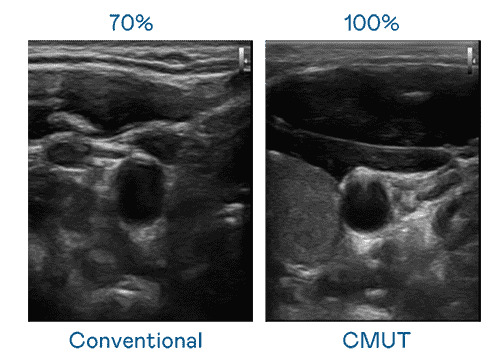

CMUT 技术是一种用电容式微机电元件来产生超音波讯号的技术。。。与传统 PZT 压电式技术相比,,CMUT 频宽增加 30%,,,更宽频的超音波讯号让影像解析度大幅提升,,是实现高影像品质医疗超音波扫描、、、、促进精准医疗发展的关键技术。。。。

大频宽带来超清晰影像

超音波影像的解析度高低,,,,首先取决于探头能发出的讯号频宽。。888.BY集团电子游戏 CMUT 可提供高清晰的超音波讯号,,提供高频宽、、高灵敏度、、、、影像纹理细节更高的超音波影像,,,,协助医护人员缩短影像判读时间及利用精准的医疗影像进行诊断。。